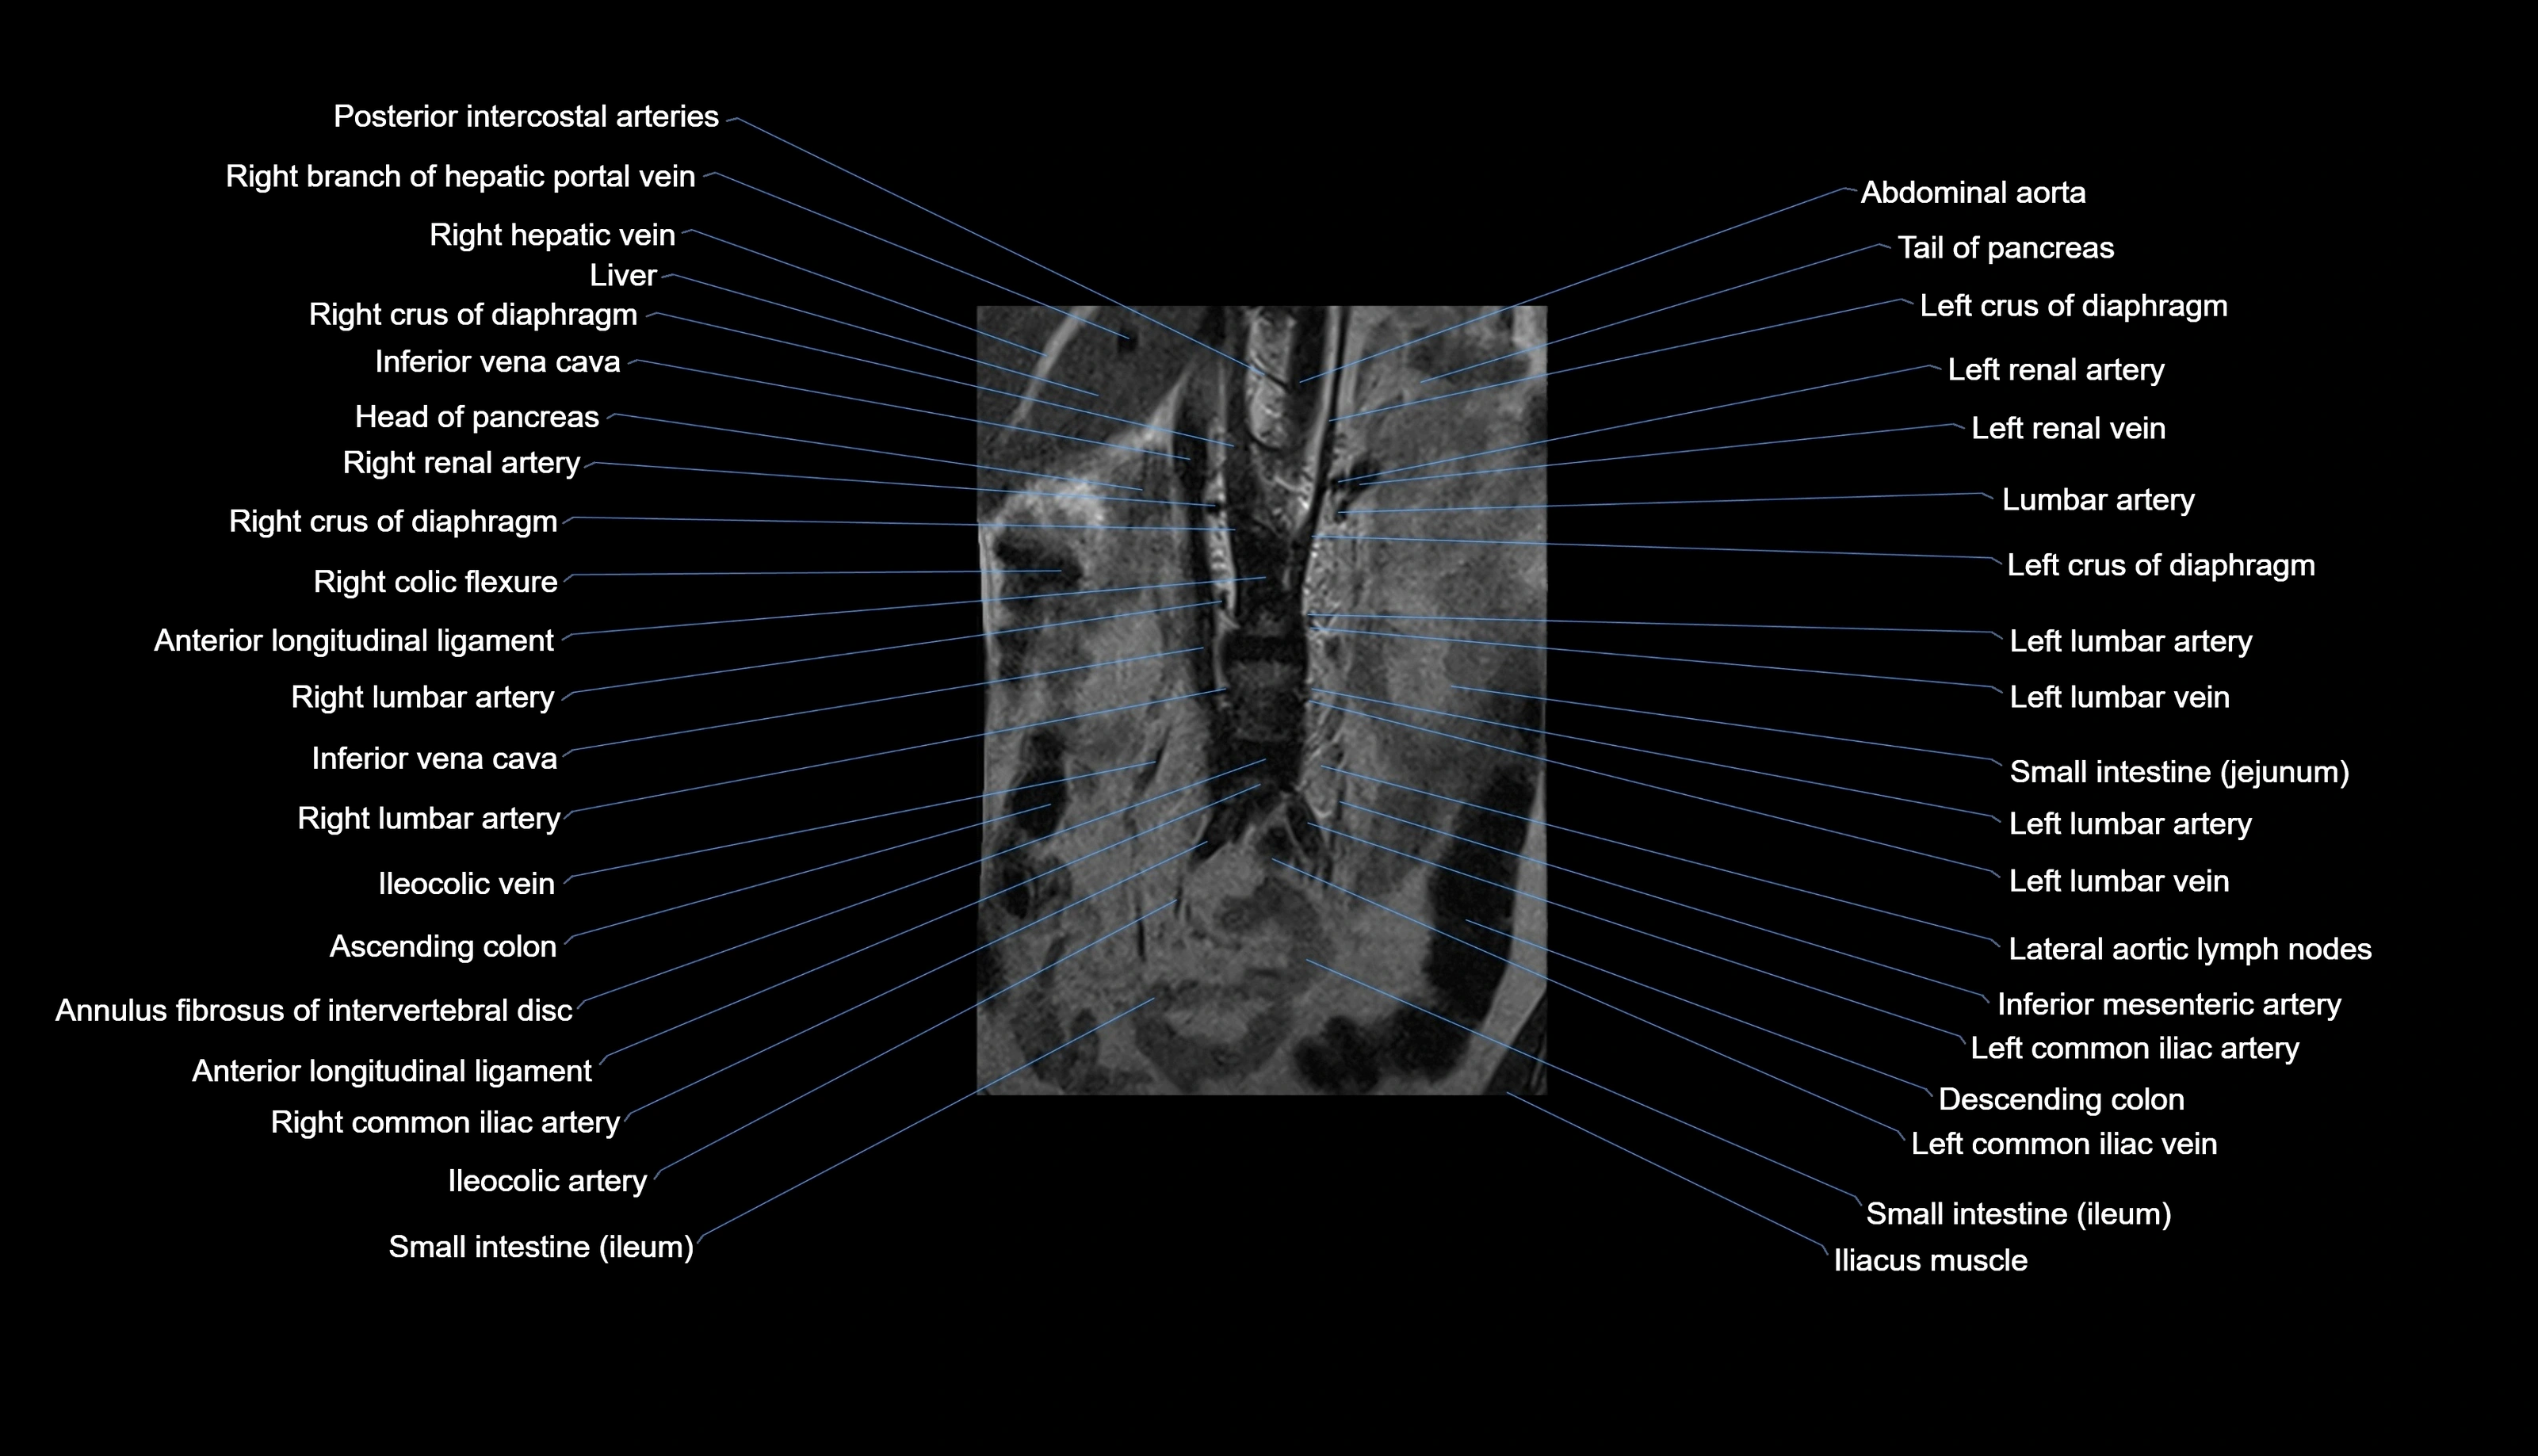

MRI images

CT images